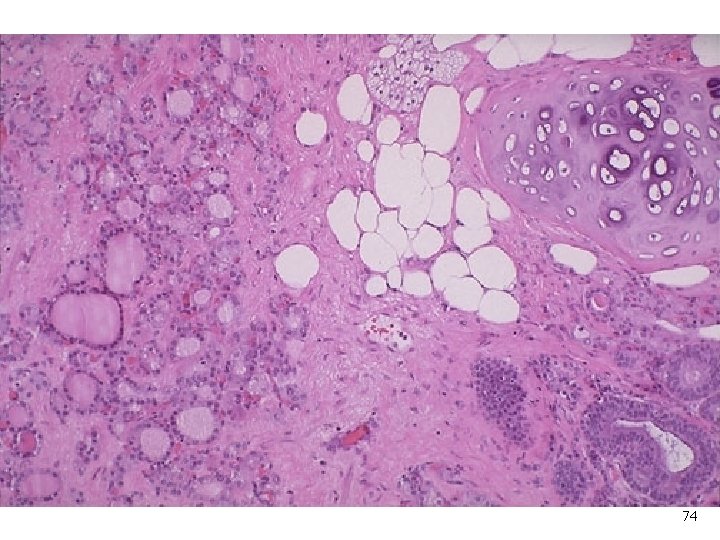

74

Figure 22 -49 Benign cystic teratoma. Low-power view of skin (top), beneath which there is brain tissue (bottom). Downloaded from: Robbins & Cotran Pathologic Basis of Disease (on 28 April 2008 01: 14 PM) © 2007 Elsevier 75